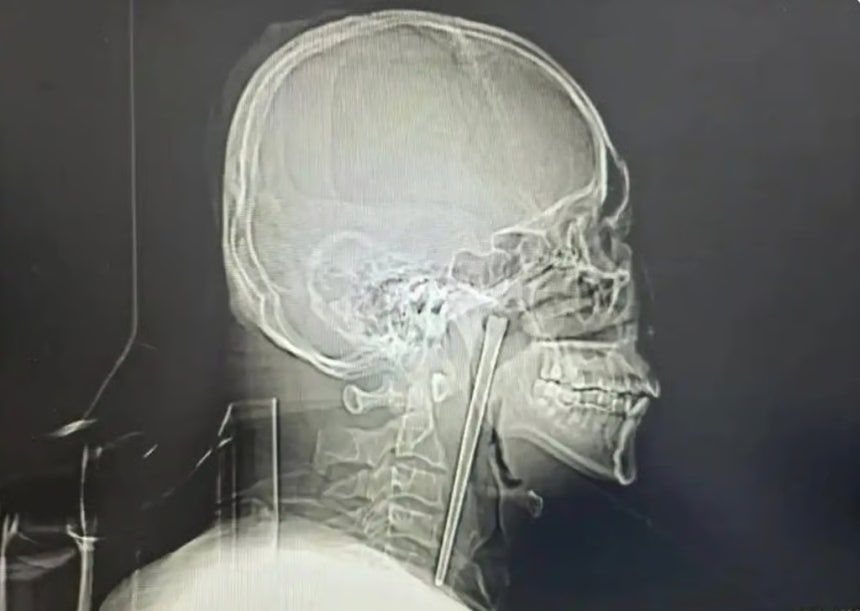

중국에서 한 남성이 길이 12㎝의 금속 젓가락이 목에 박힌 채 8년을 버티다 최근 제거 수술을 받아 눈길을 끌었다.

19일(현지시각) 사우스차이나모닝포스트(SCMP)는 왕씨가 이달 초 중국 북동부 랴오닝성 다롄시 중앙병원에서 목에 박힌 금속 젓가락을 제거하는 수술을 받았다. 보도에 따르면 왕씨는 8년 전 식사 도중 술을 마시다 실수로 금속 젓가락을 삼켰다.

정밀 검사 결과 왕씨가 삼킨 젓가락은 목 안쪽 연구개 부위에 박혀 있었던 것으로 확인됐다. 의료진은 다행히 주변 점막에 손상이 없고 성대 기능 역시 정상적으로 유지되고 있었다고 설명했다.

주치의는 “목에 젓가락이 걸려 있다고 말해 최근 발생한 일로 생각했으나 8년 전 일이라는 설명을 듣고 놀랐다”고 했다.

왕씨는 목 절개를 거부했고 의료진은 구강을 통한 최소 침습 수술을 진행했다. 다행히 젓가락은 성공적으로 제거됐다. 왕씨는 빠르게 회복해 수일 뒤 퇴원했다.